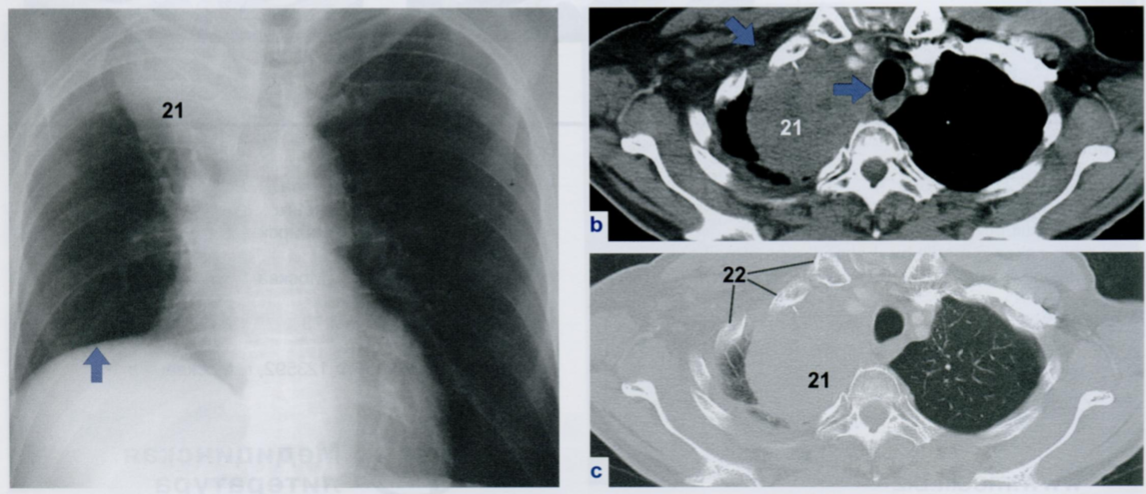

Некоторые участки плевры могут выглядеть расширенными или неровными, и это не следует принимать за патологическое утолщение.

В частности, линия париетального листка плевры хорошо видна в ЗПП (первый снимок). Она имеет волнистый характер из-за того, что повторяет анатомические контуры межреберных промежутков (сравните со вторым снимком).

На втором снимке верхушечная плевра расположена по касательной к ходу рентгеновского излучения и поэтому выглядит, как сопровождающее затенение вдоль нижнего края второго ребра (22).

На Rx снимке показан пациент с опухолью Панкоста (21) в верхушке правого легкого.

Причина высокого стояния купола диафрагмы (стрелка) на стороне поражения заключается в параличе правого диафрагмального нерва, вызванном прорастанием опухоли.

При КТ четко видна инфильтрация мягких тканей грудной стенки (косая стрелка). Также определяются неоднородная структура опухоли (21) и смещение средостения влево (горизонтальная стрелка).

Однако сканирование в легочном окне (нижнее КТ) показываст, что узурации верхних ребер (22) пока еще отсутствуют.